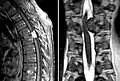

Meningeom im Spinalkanal Kernspintomographie. Links T1 sagittal mit Kontrastmittel, rechts T2 coronar

Das bildgebende Verfahren der ersten Wahl ist beim Meningeom heute die Kernspintomografie, da dieses Verfahren den größten Weichteilkontrast besitzt und in typischen Fällen die sichere Diagnose eines Meningeoms ermöglicht. In T2-gewichteten Aufnahmen stellen sich verkalkte Meningeome im Gegensatz zu vielen anderen Tumoren als schwarze Masse (hypointens) dar, die dunkler als das umgebende Hirngewebe ist. Unverkalkte Meningeome können zur Umgebung isointens sein. Von anderen Tumoren unterscheiden sich Meningeome durch ihre Lage auf der Dura mater mit charakteristischen Ausläufern in die Dura (dural tails) und durch eine sehr intensive Kontrastmittelaufnahme. Die Computertomographie kann die Tumorverkalkungen sehr gut nachweisen. Konventionelles Röntgen und Angiographie haben heute nur noch eine untergeordnete Bedeutung.

Die meisten Meningeome wachsen sphärisch oder globulär unter Beibehaltung ihrer soliden Masse. In manchen Fällen können sie Hirnhäute, Knochen oder auch venöse Blutleiter durchbrechen. Liegt eine Infiltration des Sinus sagittalis superior vor, werden die Meningeome in 6 verschiedene Subtypen nach Sindou eingeteilt.[8] Daneben beobachtet man bevorzugt im Os sphenoidale eine plaqueförmige Ausbreitung.